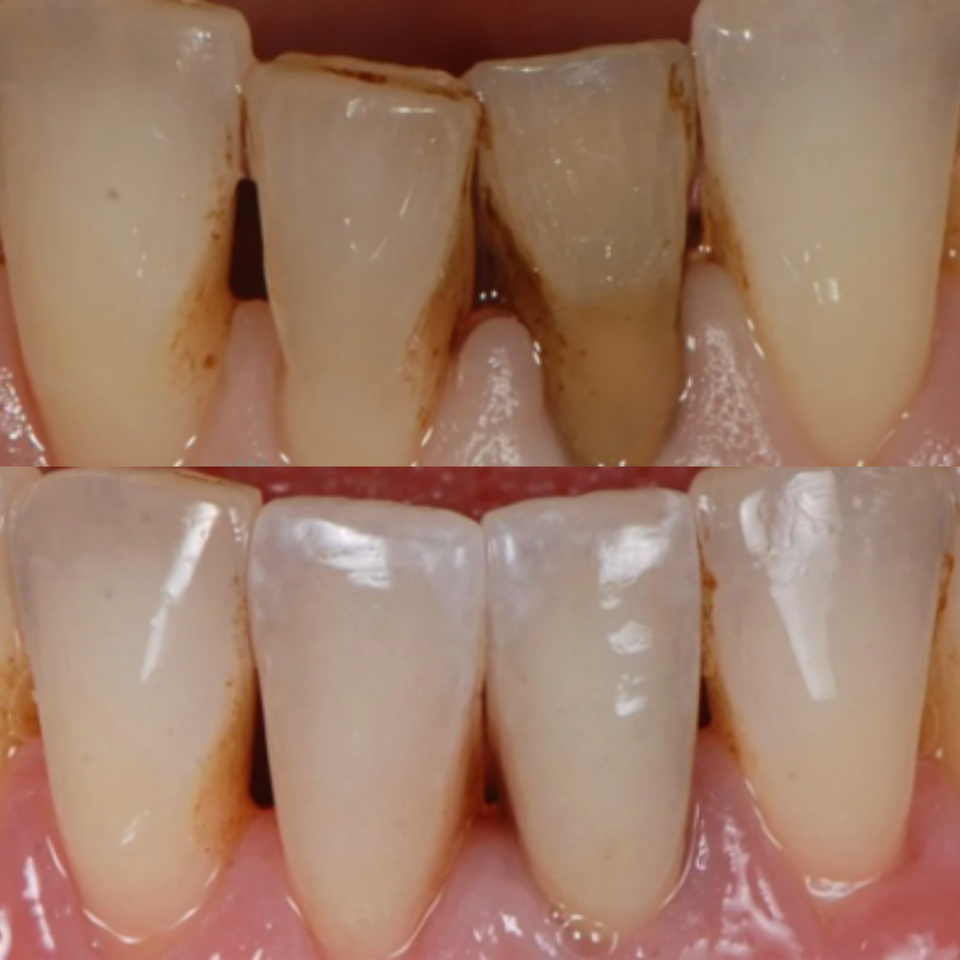

At Elite Dental Group, we provided emergency care that included root canal treatment on the upper central incisors. Dr. Satish Palayam performed an immediate implant placement for the right lateral incisor and completed a crown lengthening procedure on the palatal side of the right central incisor to support proper restoration. A provisional bridge was then placed to maintain both function and esthetics throughout the healing phase.

After a four month healing period, the final crowns were placed on the central incisors, and the implant for the right lateral incisor was successfully restored and finalized.